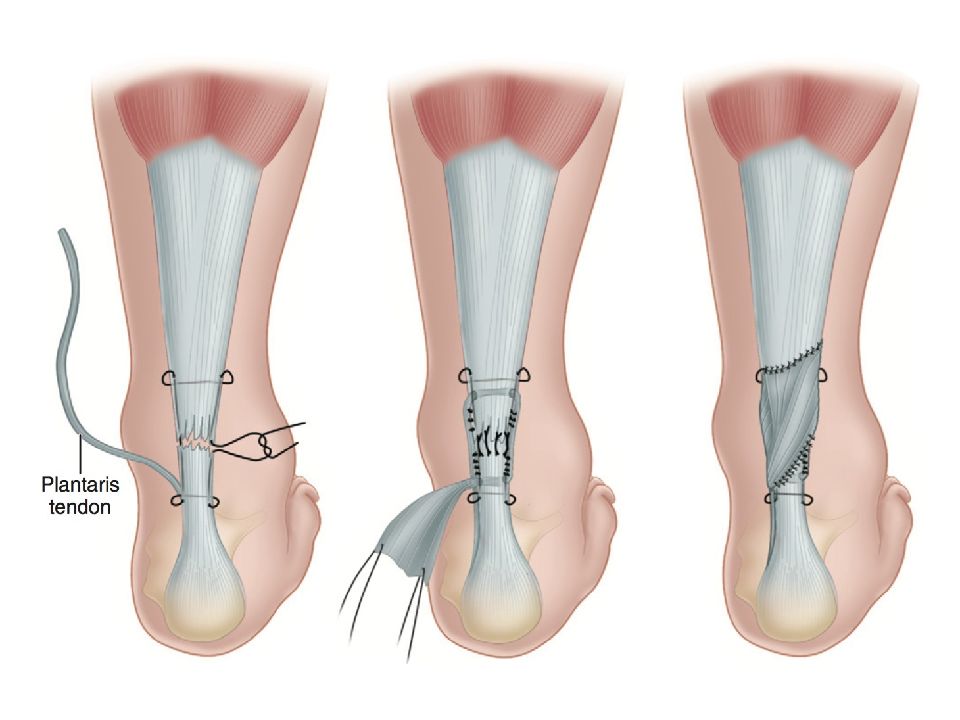

Тендинит Ахиллова сухожилия: симптомы и лечение

Раздел: Картинки на заметку